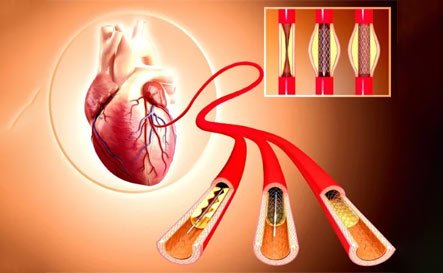

Cardiac Procedures

Coronary Artery Bypass Graft (CABG)

Angioplasty